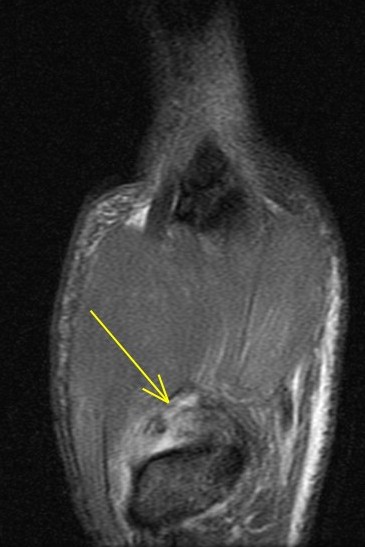

26 y/o crashed on a skateboard.

Patient has torn the deep anterior oblique ligament (beak), and sprained the superficial anterior oblique ligament, posterior oblique ligament and first intermetacarpal ligament. Also a sprain of the dorsoradial ligament. The joint has reduced but the patient related that he can slip it in and out easily. First images are from a dedicated thumb exam and the last image is from the wrist exam.

trapeziometacarpal dislocation